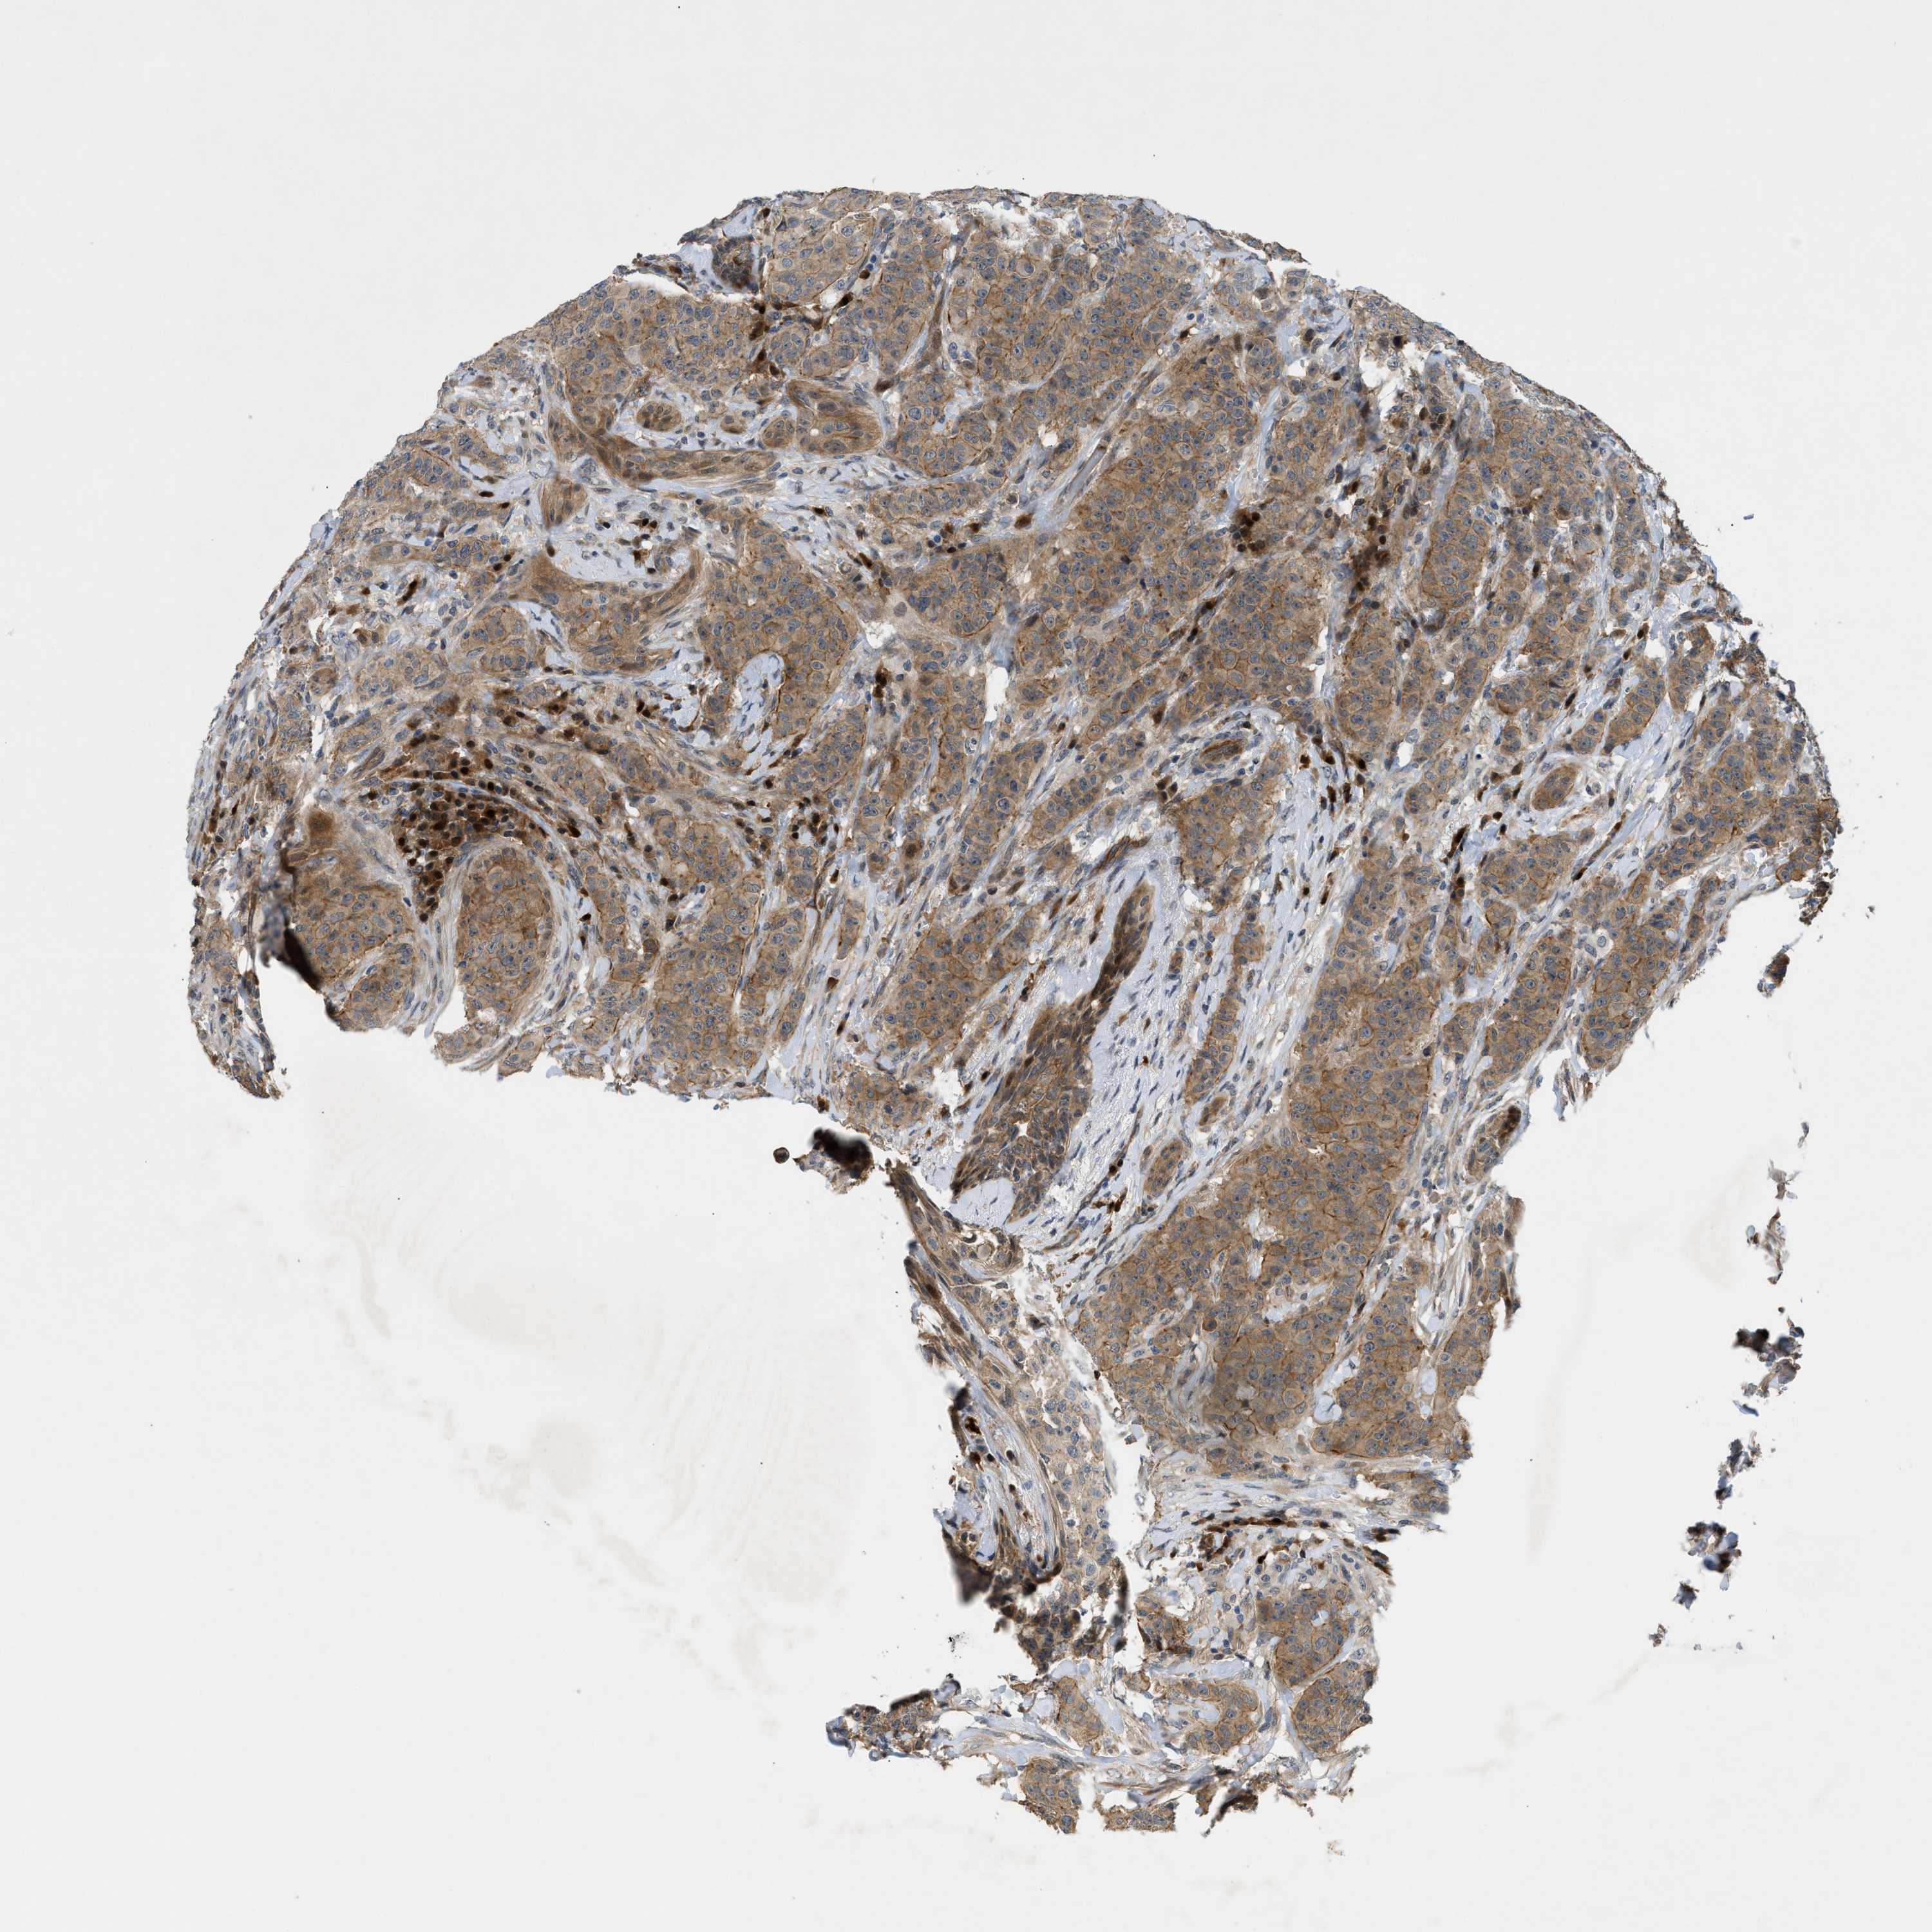

CANCER BREAST CANCER Show tissue menu

BRCA TCGA BRCA VALIDATION PROTEIN EXPRESSION